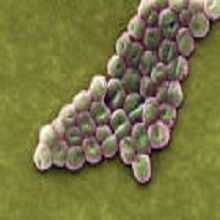

„Acinetobacter" је Грам негативан, полиморфан, стриктни аероб, распрострањен у природи као сапрофит или представља део физиолошке флоре човека (кожа, дисајни путеви и генитални тракт). То су кратки здепасти, а понекад и округласти бацили. Често имају капсулу. Каталаза су позитивни а оксидаза негативни. Често је присутан у болничкој средини (лавабои, катетери, ваздух и др). |